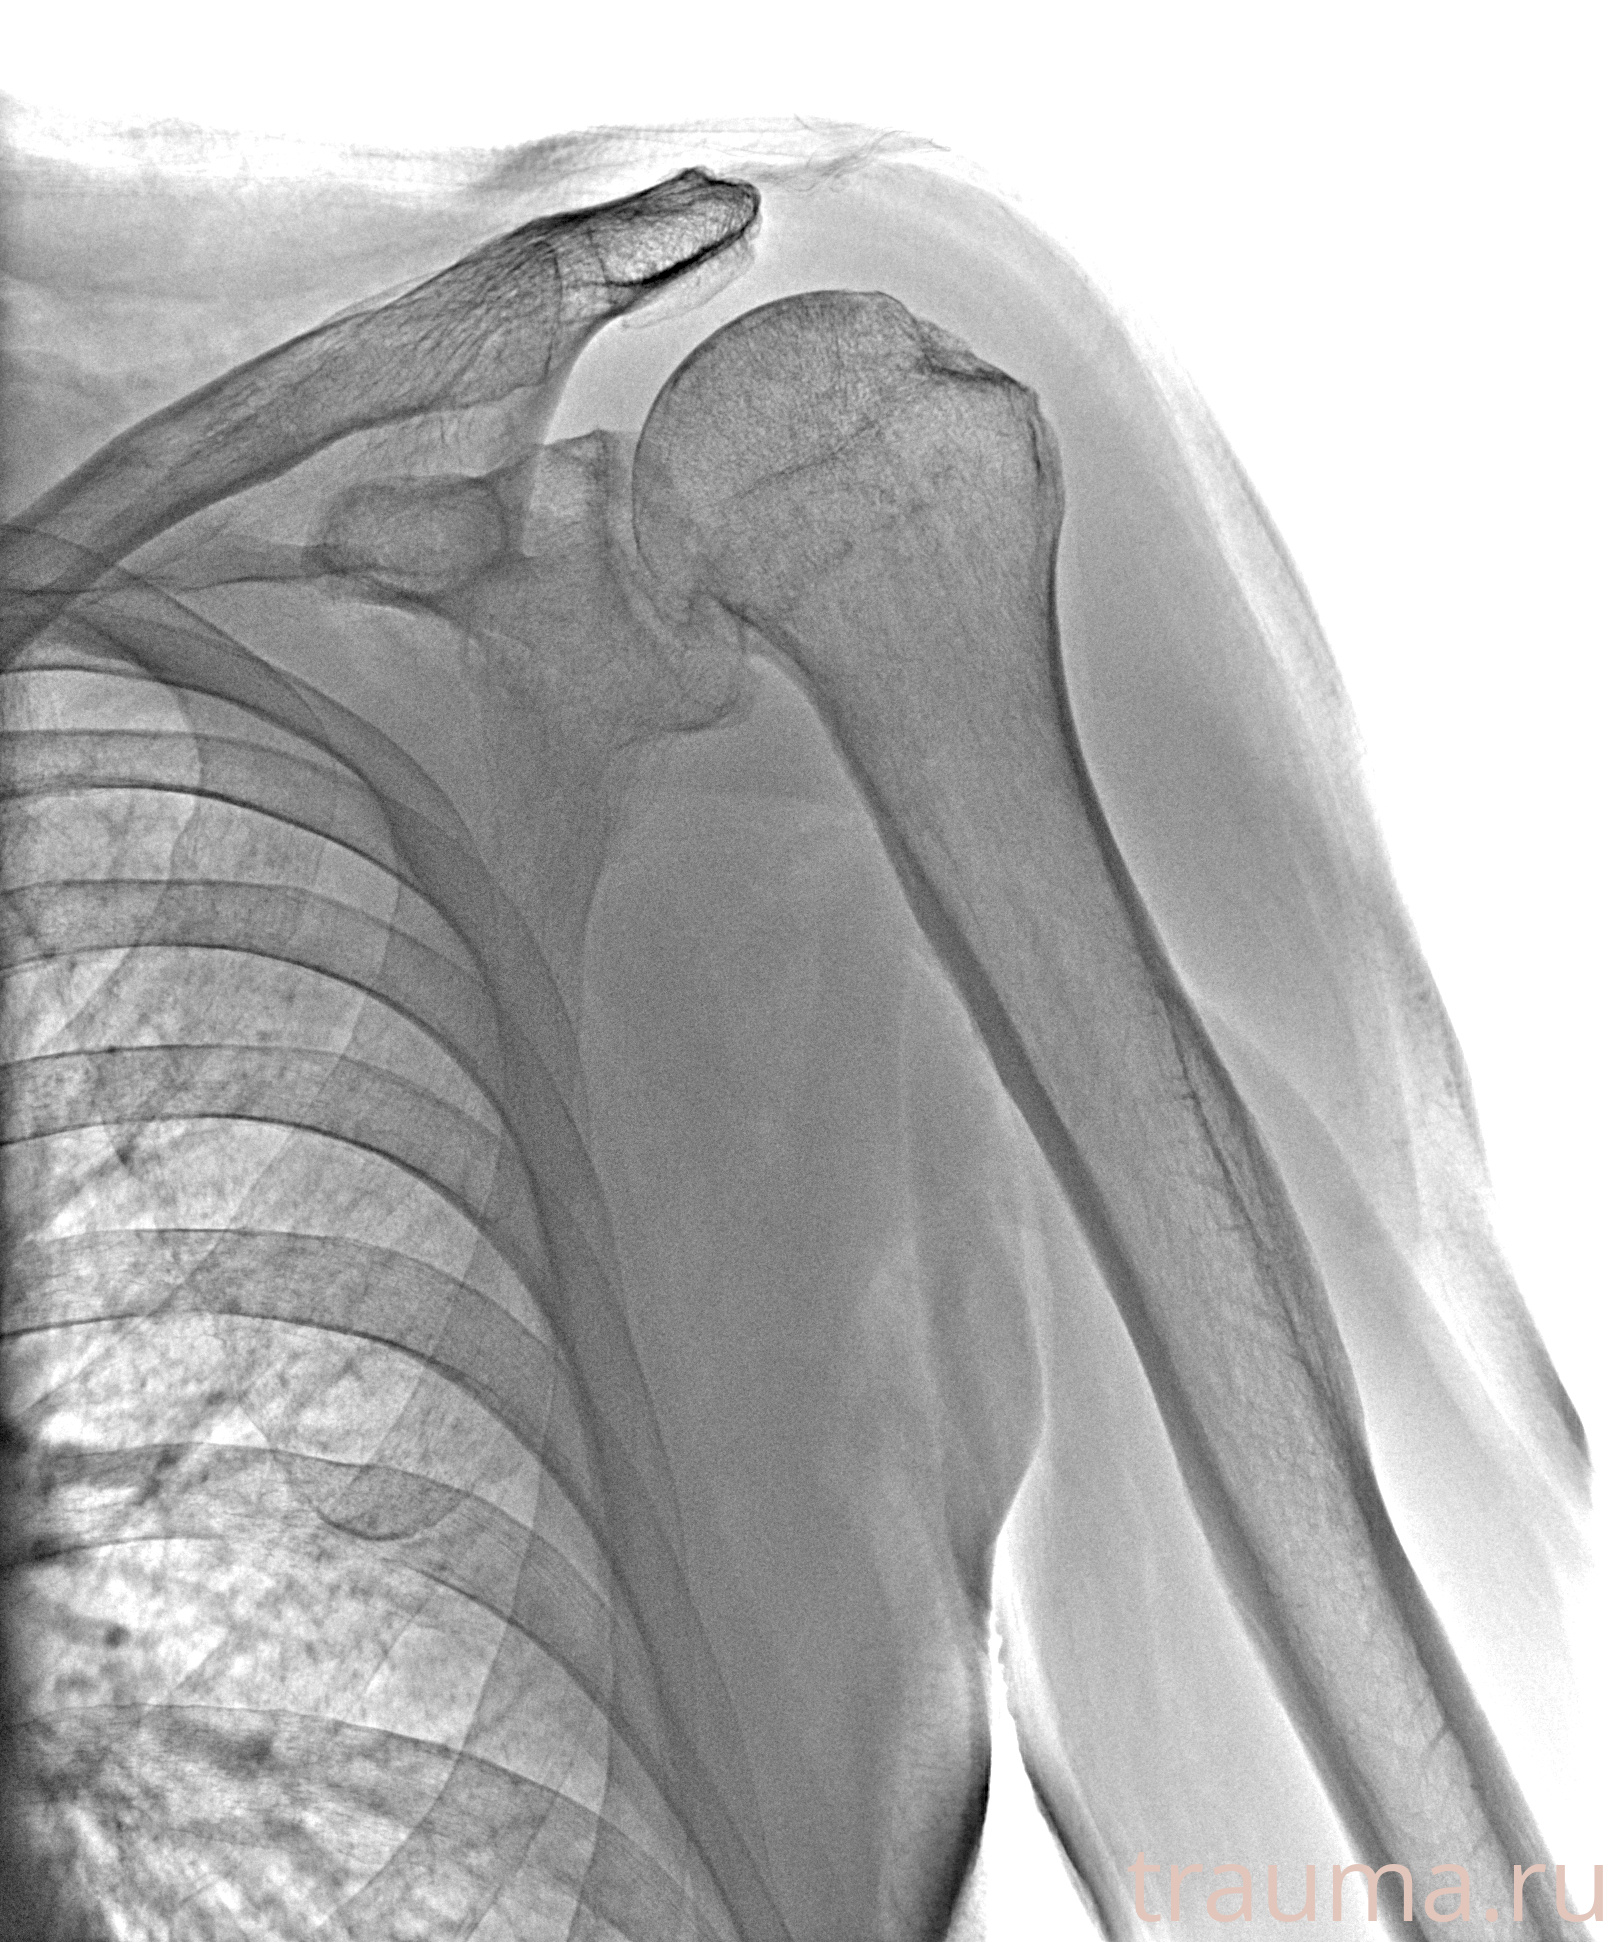

Рентгенограммы

Рентген на дому: по вашему адресу приезжает врач-рентгенолог, травматолог-ортопед с мобильным рентгеновским аппаратом, проводит диагностику травмы или заболевания, делает необходимые рентгенограммы, дает рекомендации по дальнейшему лечению. Получить качественные снимки в домашних условиях возможно благодаря уникальной методике, разработанной МосРентген Центром для института  Склифосовского